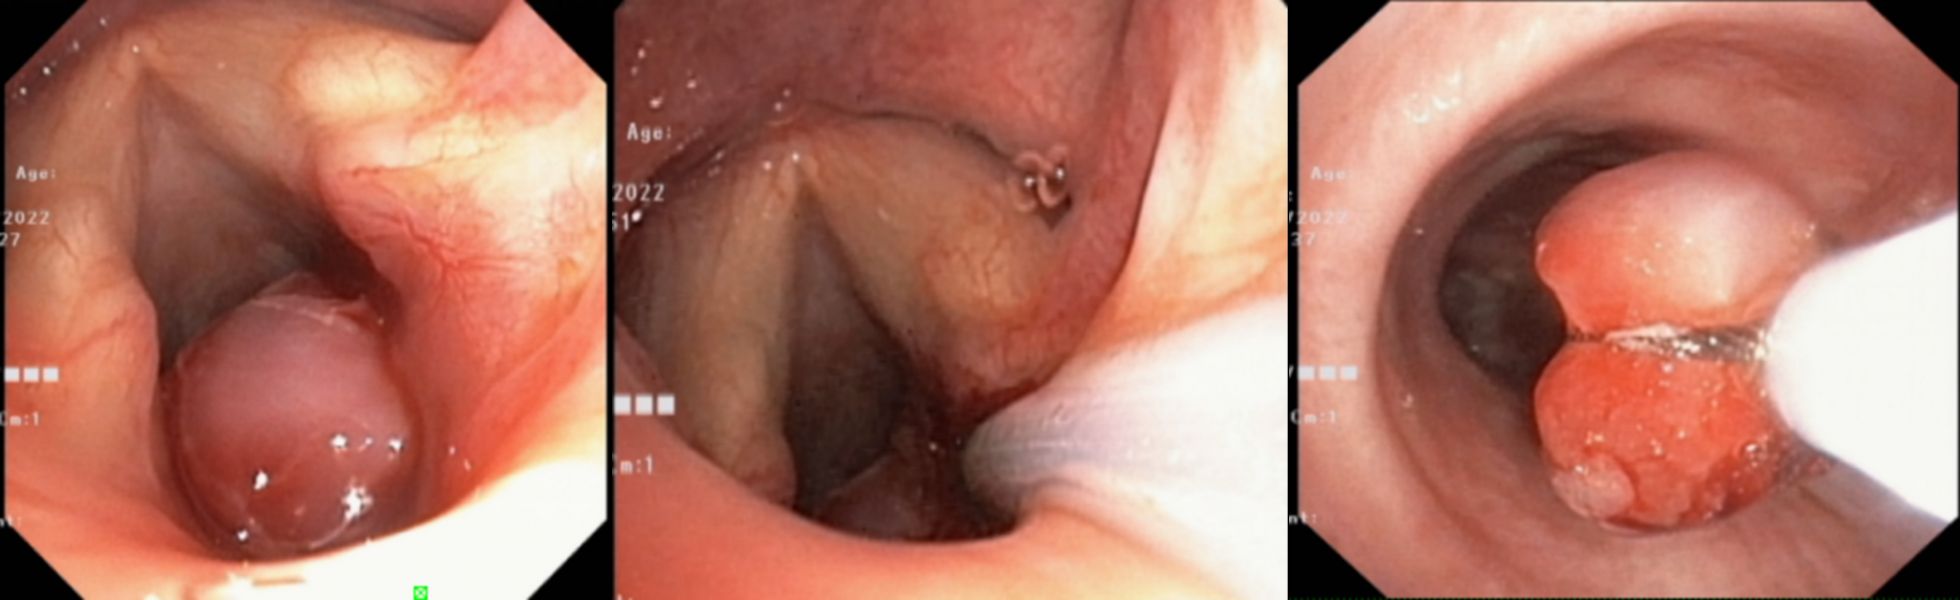

4月14日上午,在麻醉科的保驾护航下行“全麻喉罩下声门下区气管肿物圈套术”,术中在医师、护师的协助下,由王先勇主要操作,镜下可见声门下区气管的肿物,顺利将肿物套扎、切除,并将肿物予网篮取出,肿物大小约1.3cmX1.3cm,在切割面处予冷冻治疗以减少疤痕形成及新生物再次生长可能,手术过持续约1小时。术后第二、四、七天随访,患者无咯血,呼吸顺畅,喘鸣音消失。

声门下新生物(狭窄70-80%),给予电圈套治疗后取出新生物